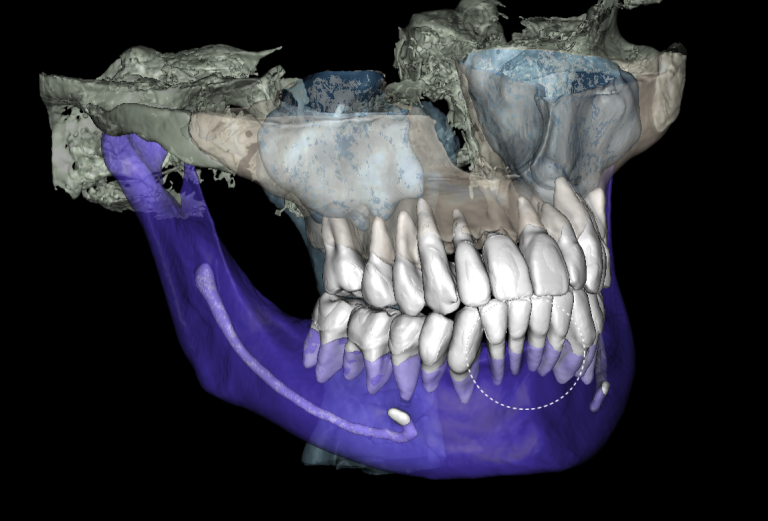

The 3D-Viewer allows the clinician to align the axes according to the area of interest and to study root canal morphology and anatomy before starting a treatment